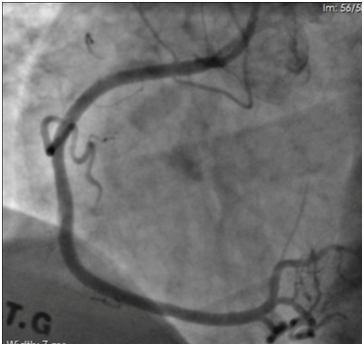

Coronary angiography revealed long, calcified > 40mm length lesion in right coronary artery proximal and middle part (Figure 1). Our decision was to treat this coronary lesion with BRS (Absorb BRS; Abbott Vascular, Santa Clara, CA, USA), following our centre plaque modification strategy, which is plaque modification before scaffold implantation using cutting or scoring balloon. In this case we used cutting balloon pre-dilatation 3.5x15mm 13 bars for each segment three times. Vessel dimensions were pre-analyzed with imaging methods to choose appropriate pre-dilatation balloon size. “PSP (Predilatation, Sizing, Post-dilatation) technique” that improves Absorb implantation is now widely described. Our centre following updated technique which is “IPSP (Imaging, Predilatation, Sizing, Postdilatation” technique. After plaque modification three BRS were implanted with total length 68mm. All scaffolds were implanted with small overlap to avoid uncovered gap which can provoke flow disturbances and possible future problems. Scaffold diameter was 3.5mm. An optimal scaffold apposition to vessel wall was achieved with non-compliant balloon 4.0x20mm. Post-dilatation was done with 15 bars in each segment. Mandatory for this intervention are imaging methods – intravascular ultrasound (IVUS) and optical coherence tomography (OCT). IVUS was performed before PCI, after plaque modification and after BRS implantation (Figure 2). OCT was performed after BRS implantation (Figure 3). Final angiography showed good result of procedure (Figure 4). Patient discharged next day on dual anti-platelet therapy for two years. Now patient reached six-month clinical follow-up with no cardiovascular events or bleeding.

Figure 4 Final angiography image for right coronary artery with good scaffold apposition.